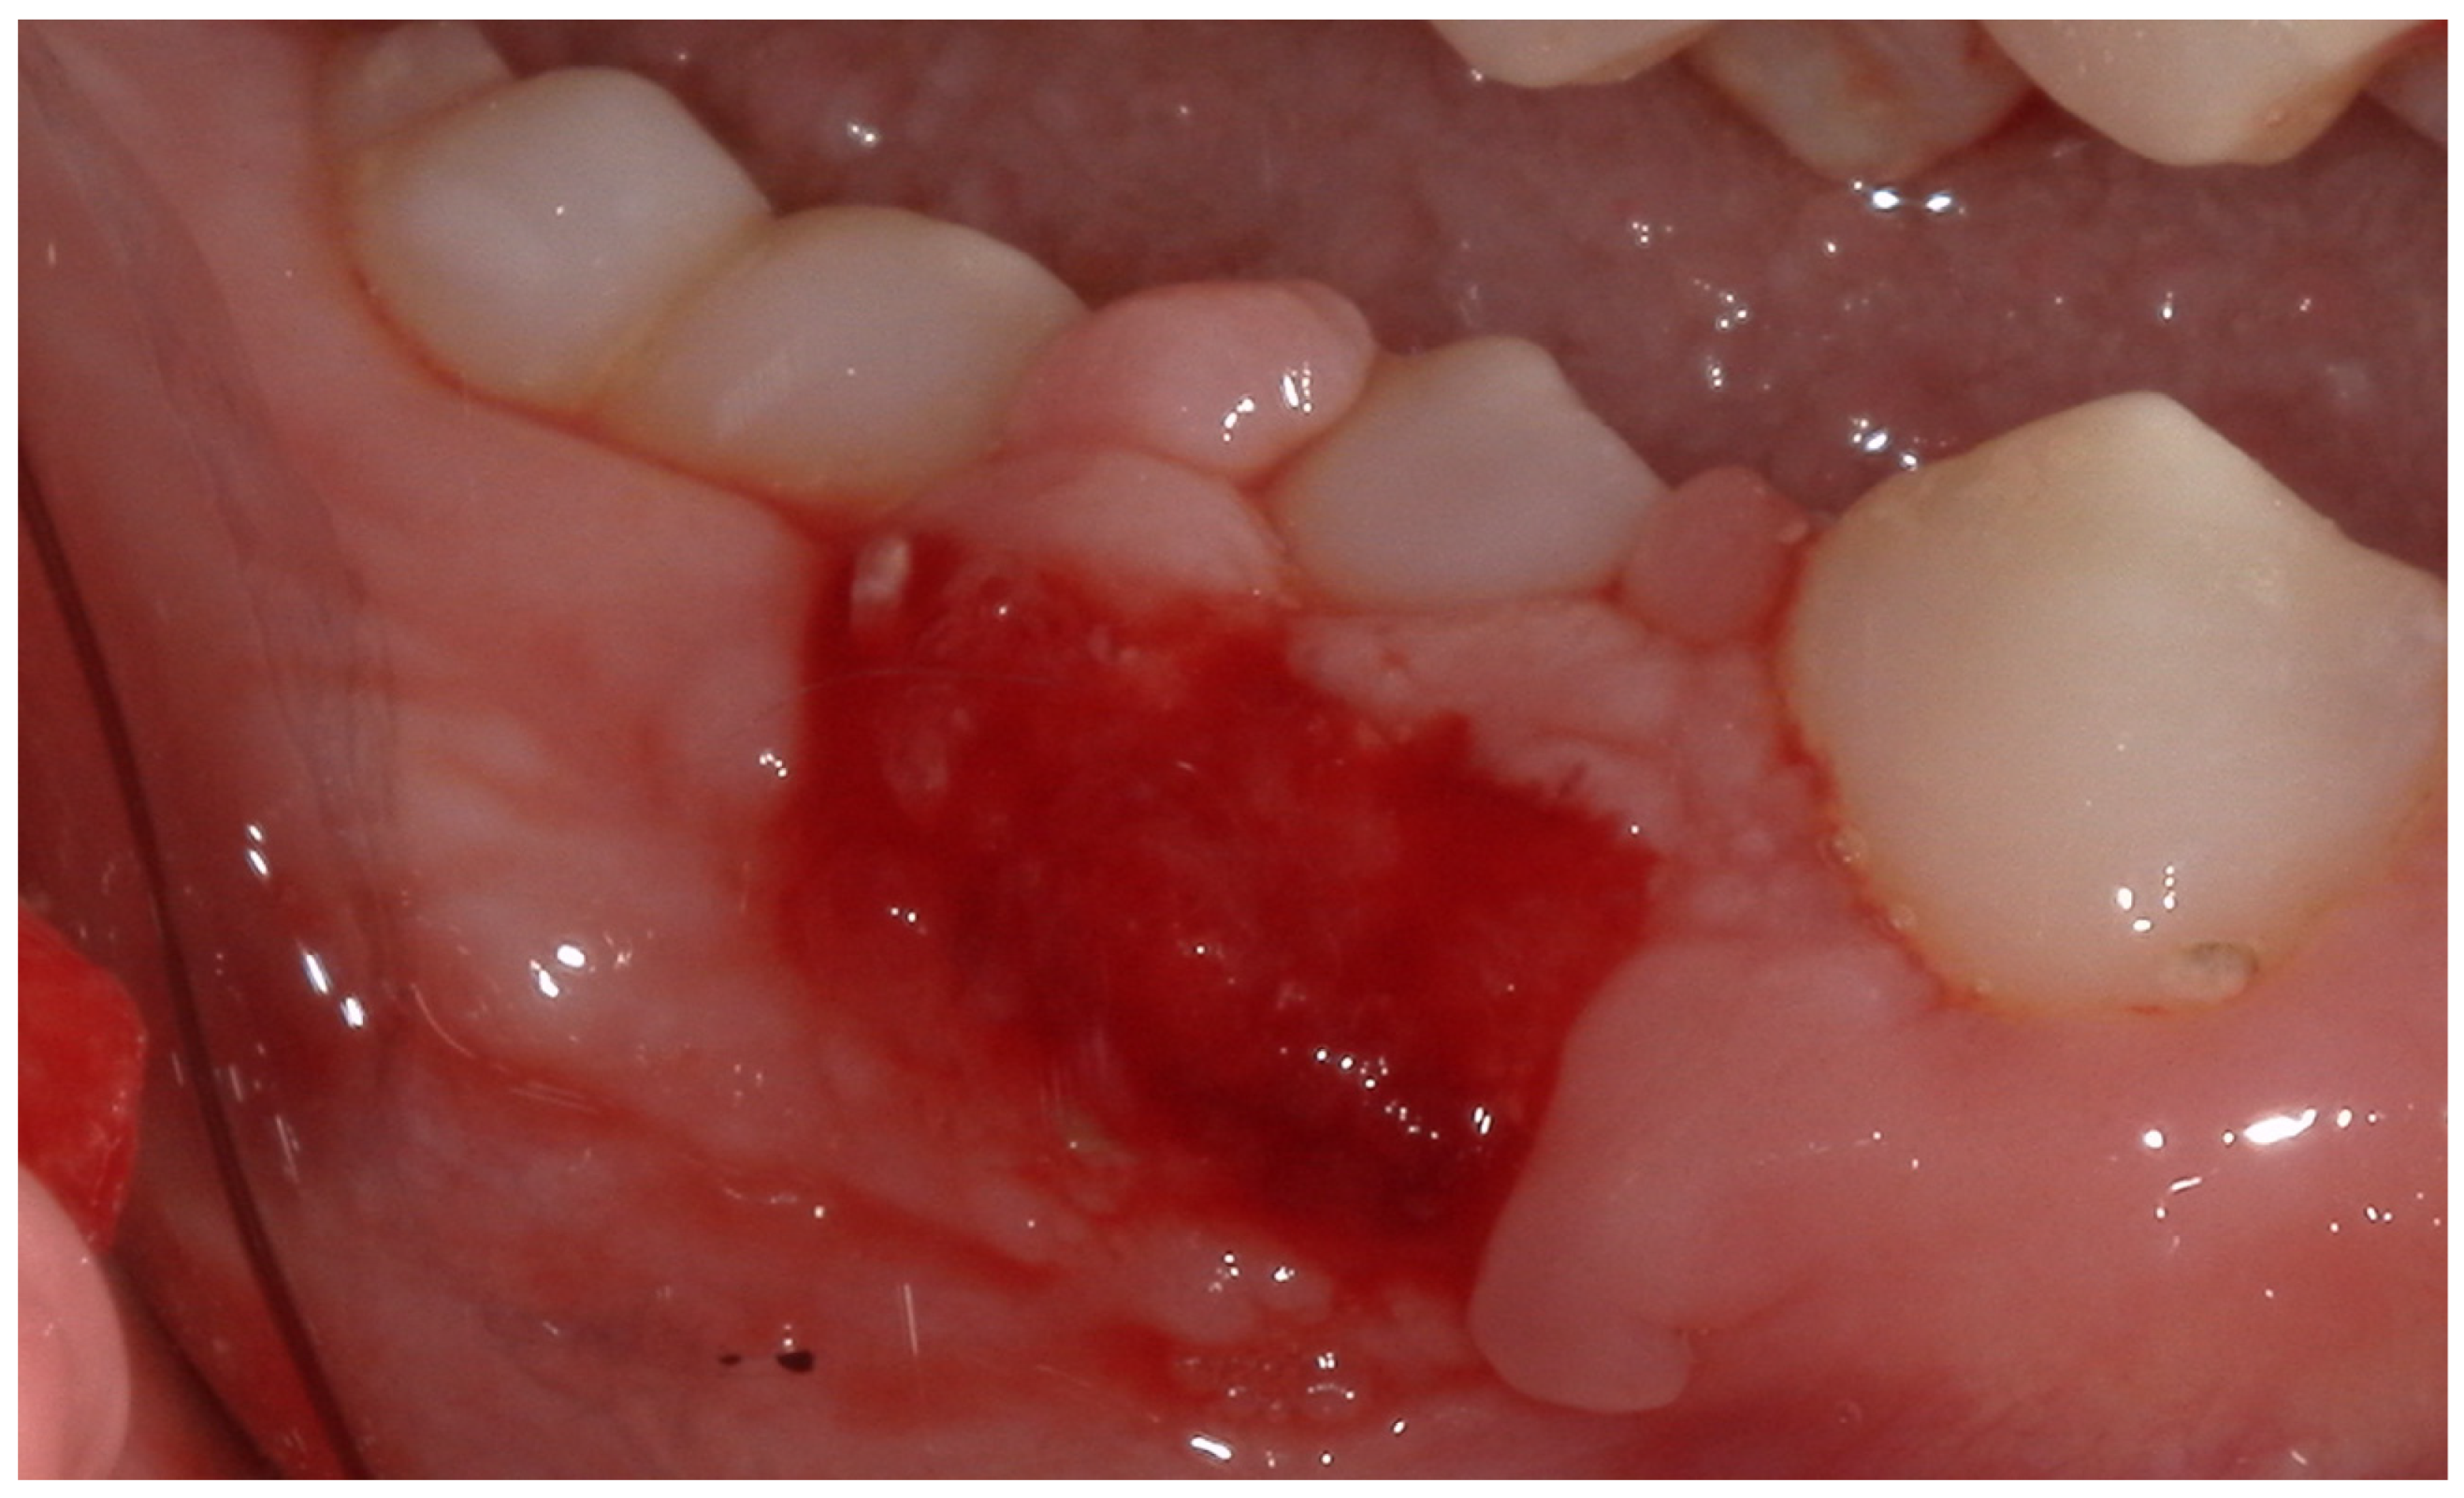

2.2. Clinical Findings

2.3. Diagnostic Assessment

2.4. Therapeutic Intervention